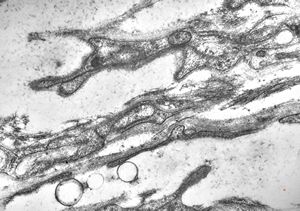

F,31y. | hypertrophic demyelinating neuropathy - n.suralis